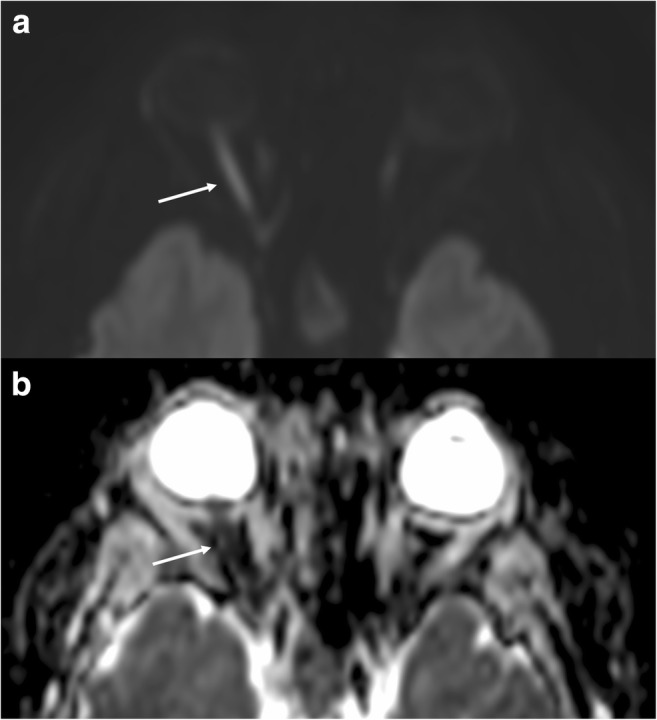

Abnormal signal intensity of the optic nerve due to diffusion restriction may be seen in ischaemic or traumatic optic neuropathy [74, 75]. DWI has been suggested as a useful tool in differentiating these aetiologies from acute optic neuritis (presumed autoimmune aetiology) [76, 77], where there is increased diffusivity in demyelinating plaques, related to disruption of myelinated axons, and decreased fractional anisotropy. However, this should be interpreted in the clinical context, since optic neuritis may also show transient decreased diffusion in the acute phase (Fig. 11).

Fig. 11.

Optic neuritis. High DWI signal (a) and low ADC value (b) representing restricted diffusion in the right optic nerve in a patient with non-specific optic neuritis